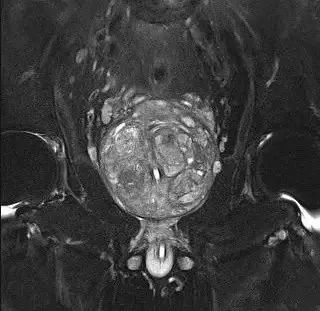

于是,李大爷抱着试一试的态度来到了深医泌尿外科,刘增钦医生为李大爷进行了前列腺超声及核磁共振检查,证实他的前列腺接近罕见的300克。

△ 术前核磁共振成像

经过深医泌尿团队的多次讨论,认为“经尿道等离子剜除术”这个方案最佳,但挑战也非常大。因为前列腺增生微创手术治疗的难度及风险会随前列腺体积的增加而上升。大体积前列腺一般为60克以上,各大权威指南认为80~100克前列腺增生不适合行经尿道前列腺电切术。